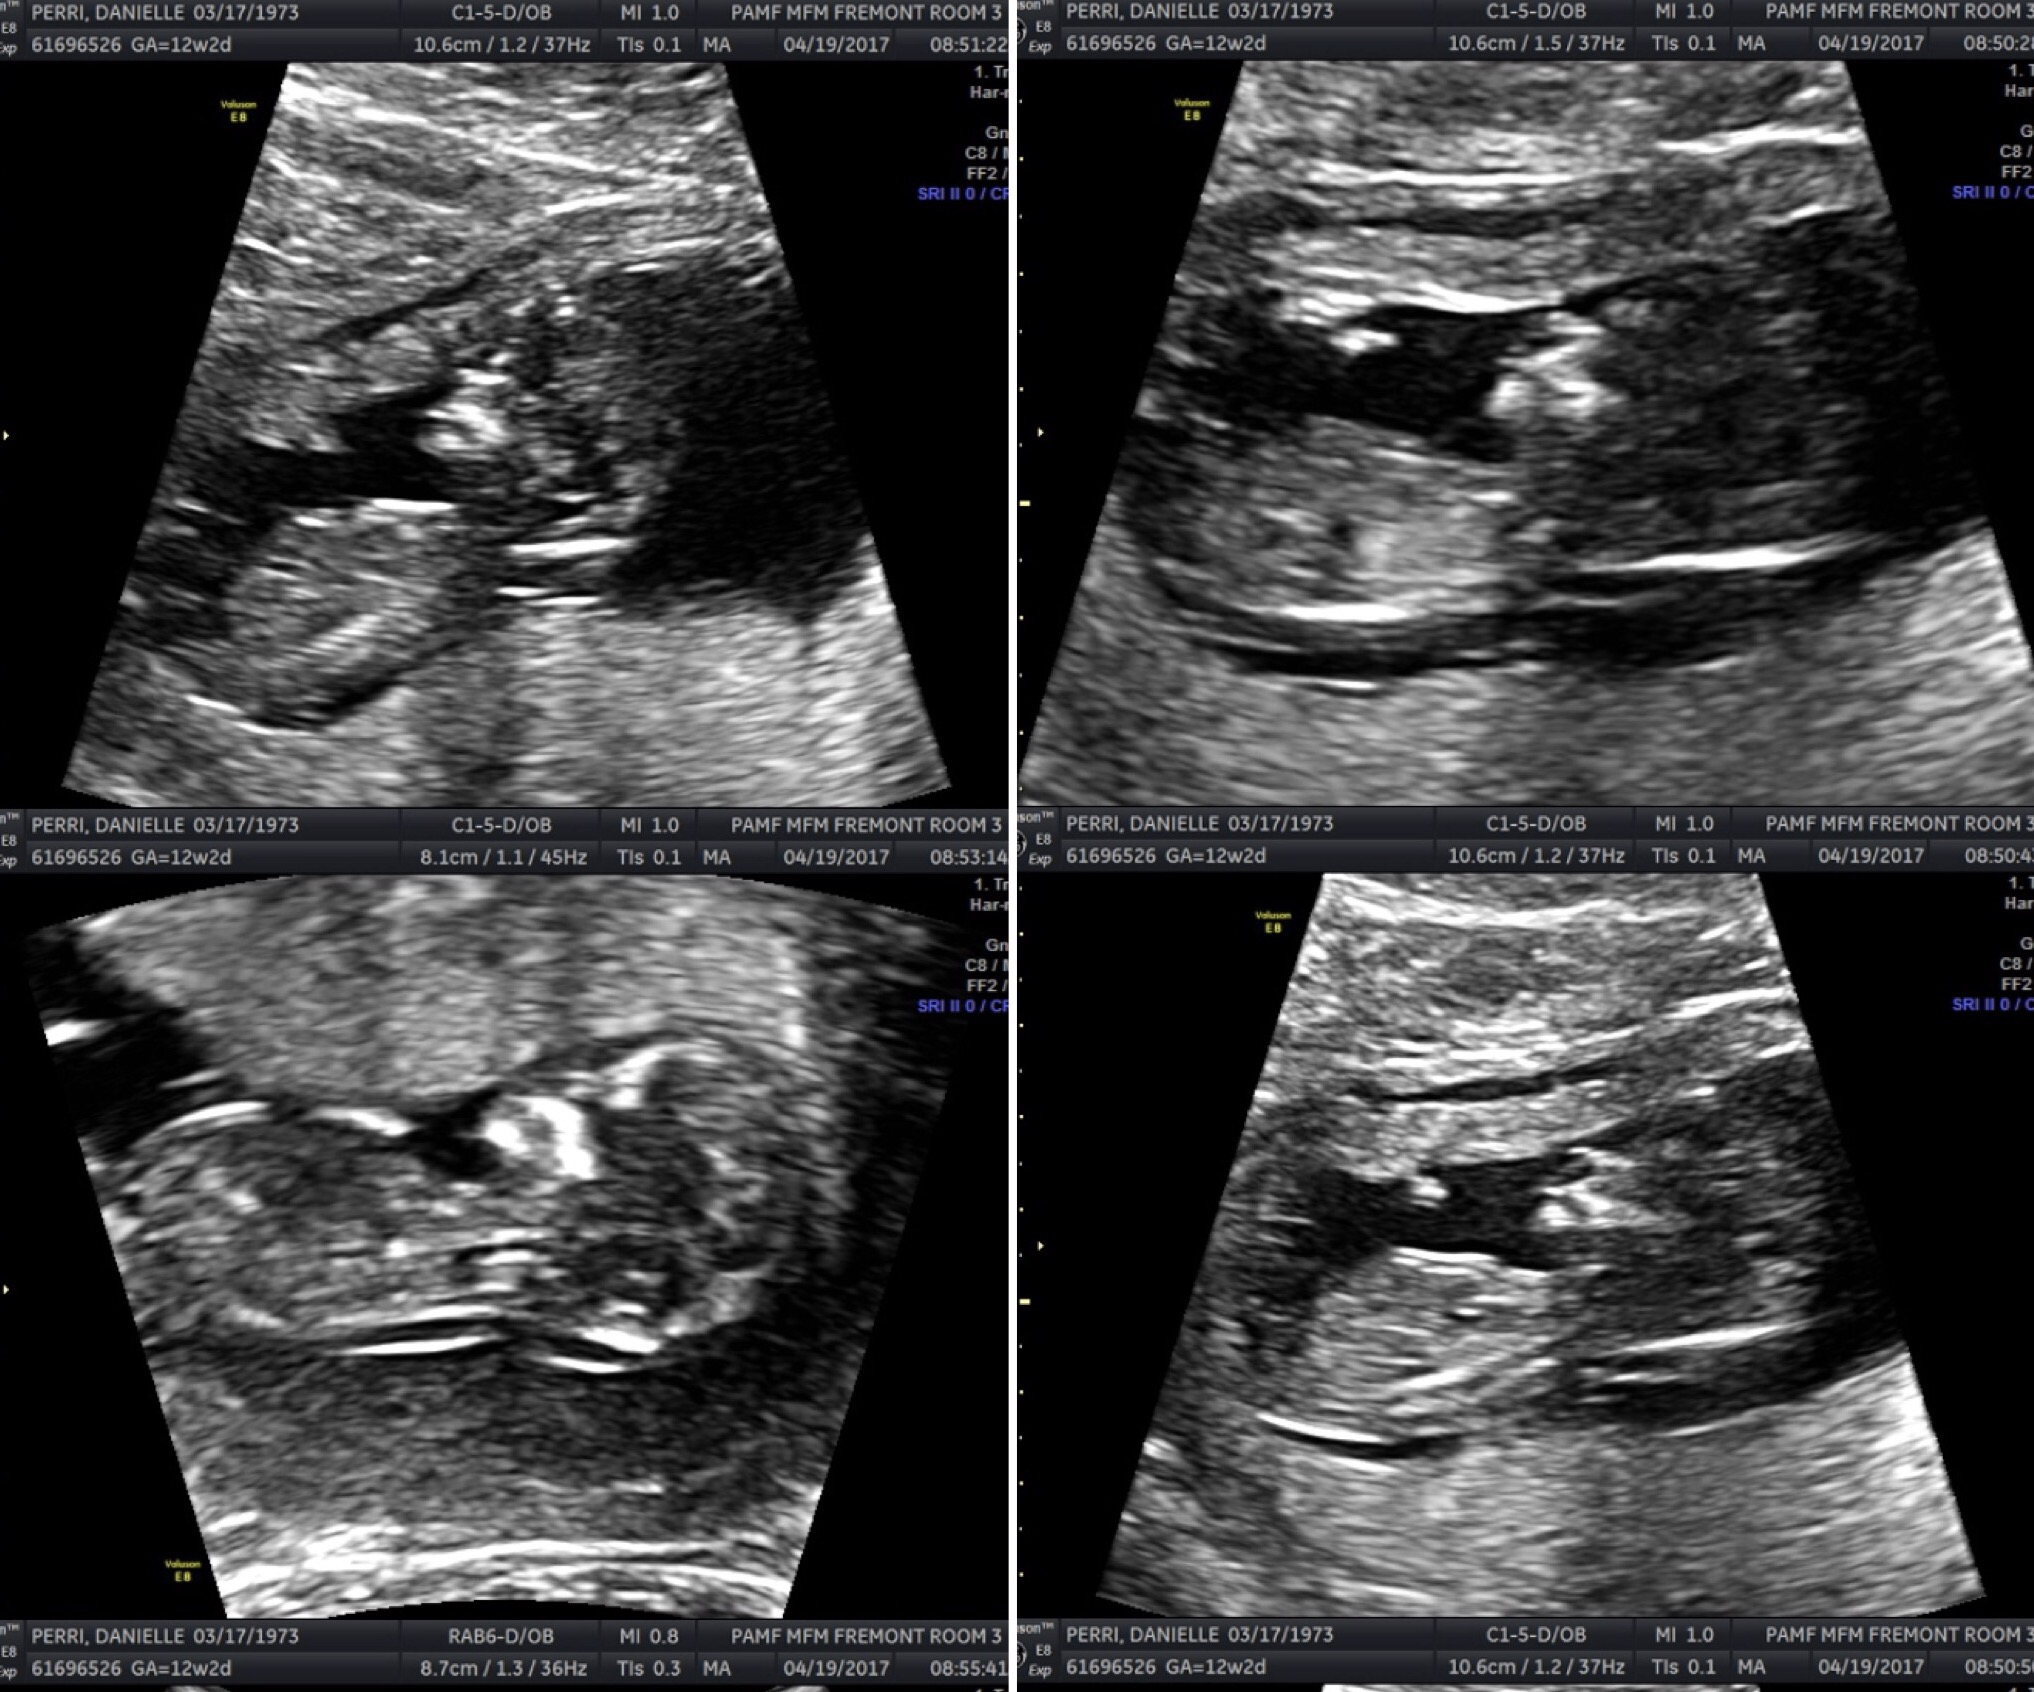

A few good things did happen at the appointment including a fun set of new ultrasound pics. Baby Perri stood on his or her head at the beginning and the tfirst ch had to wiggle my stomach to get the baby to wake up. The pics in part made up for how uncomfortable the test was, which despite having a more full bladder than normal still get like little deep punches.

Our baby’s ultrasound was pronounced normal which helped for the rest of the news today. The baby’s transnucal fold was 2.3. The tech had told me that anything under 3 was normal, so not knowing my blood test results I was shocked to be told my new combined risk, made up of my formula that combined fold and blood test results produced a positive test, meaning I had a higher risk of having a baby with Down’s Syndrome. However my results did Edwards Syndrome is 1/680 which is negligible and good news.

All I can do now is wait and hope and pray, all of which I’m doing and try to stay unstressed perhaps in part via humor. Looking through the images I was given on CD, I fondly remembered telling the tech this one made the baby’s face look like s/he was wearing a Lucha Mask and without me telling her what I mean she did agree it looked a bit like the Mexican masks below the photo.